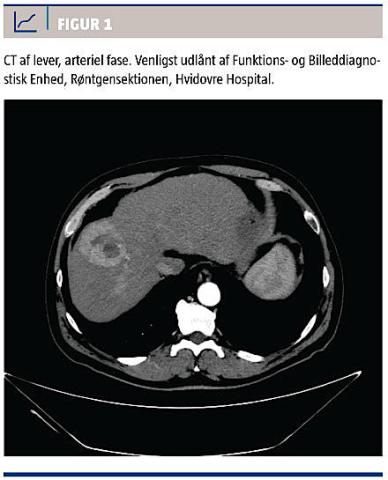

I. En 59-årig tidligere rask mand fik pneumoni, og forløbet var mere langtrukket end forventeligt, hvorfor patienten hos egen læge blev udredt med et bredt panel af blodprøver. Disse viste forhøjede levertal og efterfølgende positiv HCV-RNA. I hospitalsregi stillede man diagnosen KHC på baggrund af en positiv HCV-RNA og et intravenøst stofmisbrug mellem 1971 og 1985. Patienten havde siden da været stoffri, men huskede symptomer (gulsot og kitfarvet fæces), der er forenelige med akut hepatitis i 1970’erne. Alfaføtoprotein (AFP)-koncentrationen var 78 mikrogram/l (normalt < 14 mikrogram/l) og alaninaminotrans-

ferase (ALAT)-niveauet var 153 E/l (normalt 10-70 E/l) på henvisningstidspunktet. På grund af den forhøjede AFP-koncentration blev patienten henvist til trefaset CT af abdomen, hvorved man fandt tre malignitetssuspekte processer, der var forenelige med HCC (Figur 1).